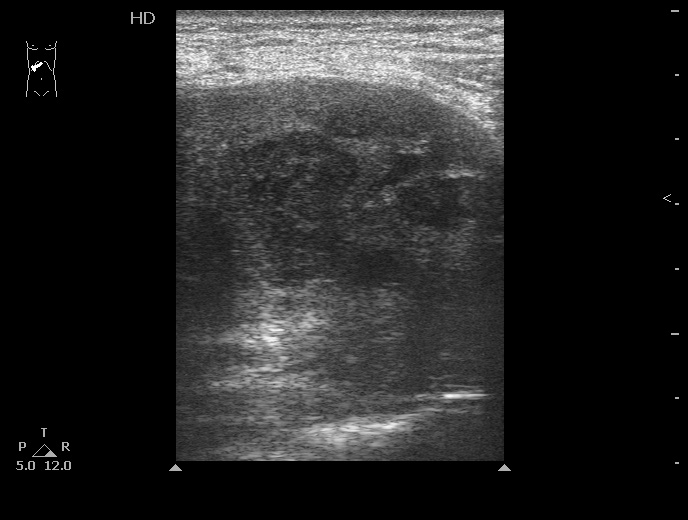

#4

10-05-25-160802_4210_201005.jpg

Типичная картина ##1-4:

Гипоэхогенное неоднородное округлое образование, окруженное эхогенным "демаркационным валом"

измененной паренхимы печени.